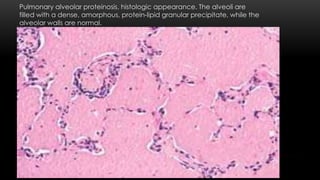

Pulmonary alveolar proteinosis, histologic appearance. The alveoli are

filled with a dense, amorphous, protein-lipid granular precipitate, while the

alveolar walls are normal.

Morphology. Characterized by apeculiar homogeneous, granular precipitate within the alveoli. Minimal inflammatory reaction Causing focal-to-confluent consolidation of large areas of the lungs with minimal inflammatory reaction. On section, turbid flud exudes from these areas. Marked increase in the size and weight of the lung